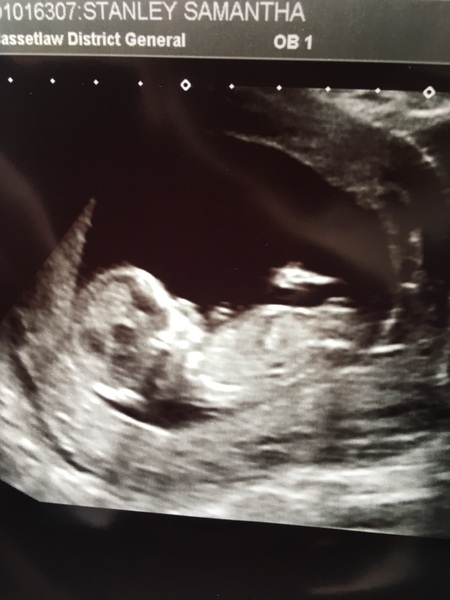

Anyone want to have a guess pink or blue?!

Nub theory...pink or blue?! We find out in 3 weeks Smile